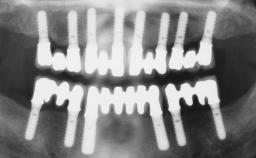

Transition from an “irrational to treat” Maxillary Dentition to a Full-Arch Segmented FDP by Early Loading of Eight Implants Placed Using the Staged Approach

The staged approach permits the transition from an “irrational to treat”dentition to a full arch implant supported restoration without any need to use a removable provisional prosthesis or to apply the immediate-placement and immediate-loading techniques.  A failing dentition is the usual indication for a staged treatment. On the other hand, the dentition should still contain many residual teeth, but with few or none of them being suitable for use as definitive abutments for a full-arch fixed restoration.This situation is usually the result of advanced periodontal disease or of the failure of an extensive fixed prosthesis.

# of Implants 8

Type of Implants One-Piece